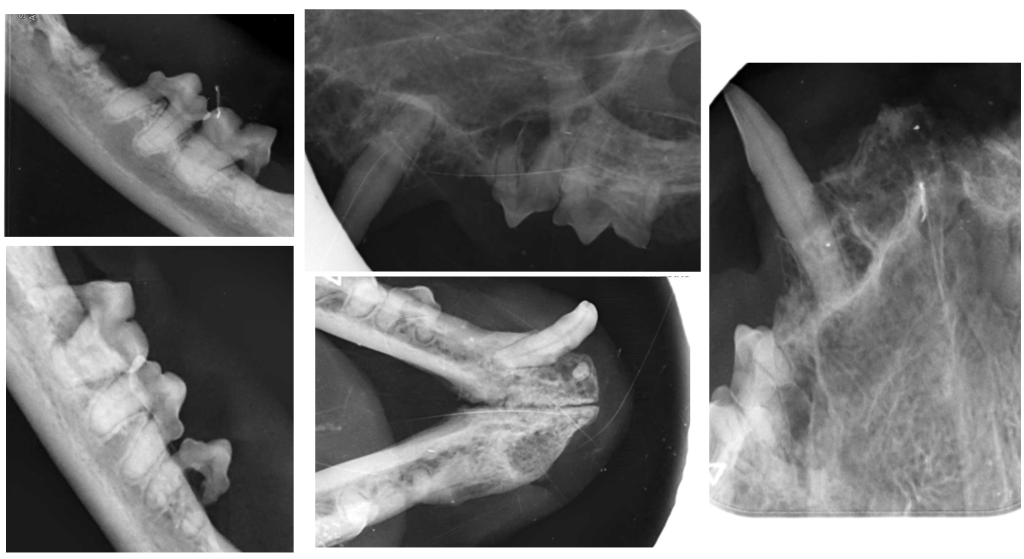

Лечение. Выполнены тотальное удаление зубов под контролем рентгенографии и альвеолопластика. Проведены кюретаж лунок и наложение швов (фото 4, 5).

Результат лечения. После операции пациент не демонстрировал симптомов боли, у него улучшился аппетит, появилась прибавка в весе. На контрольных осмотрах наблюдалась положительная динамика состояния слизистой оболочки полости рта (фото 6, 7), поэтому к дополнительным методам лечения не прибегали.

Лечение. Проведены тотальное удаление зубов под рентгенологическим контролем, альвеолопластика, кюретаж и наложение швов (фото 10, 11).

Результат лечения. Спустя 4 месяца контрольный осмотр показал улучшение качества жизни пациента с положительным ответом на хирургическое лечение (фото 12).